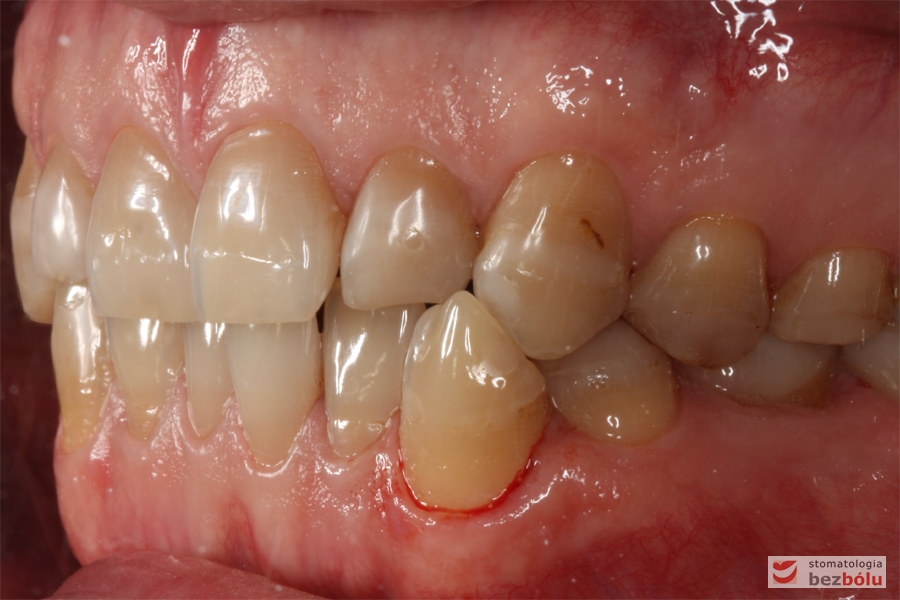

Zęby w zwarciu - strona prawa, przebarwienia świadczące o chorobie szkliwa (hypoplazja)

Zęby w zwarciu – strona prawa, przebarwienia świadczące o chorobie szkliwa (hypoplazja)